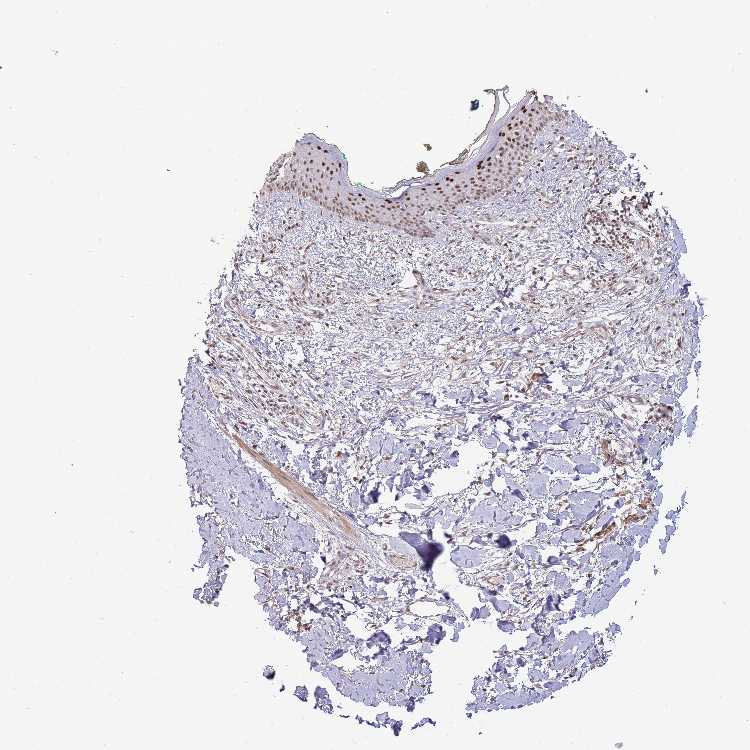

SKIN 1 - Antibody stainingi

Antibody staining in the annotated cell types in the current human tissue is reported as not detected, low, medium, or high, based on conventional immunohistochemistry profiling in selected tissues. This score is based on the combination of the staining intensity and fraction of stained cells.

Each image is clickable and will lead to virtual microscopy that enables deeper exploration of all samples and also displays staining intensity scores, fraction scores and subcellular localization as well as patient and tissue information for each sample.

Antibody HPA046387Antibody CAB037214Antibody CAB037285

Langerhans Not detectedNot detectedMedium

Fibroblasts MediumNot detectedMedium

Keratinocytes HighMediumHigh

SKIN 2 - Antibody stainingi

Epidermal cells HighHighHigh